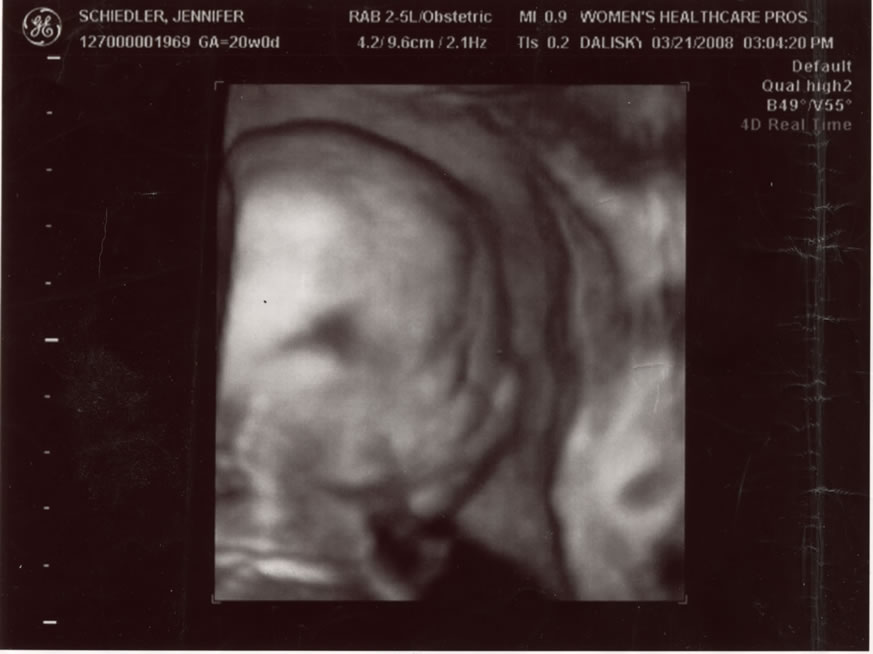

Anther profile.  4 of 5